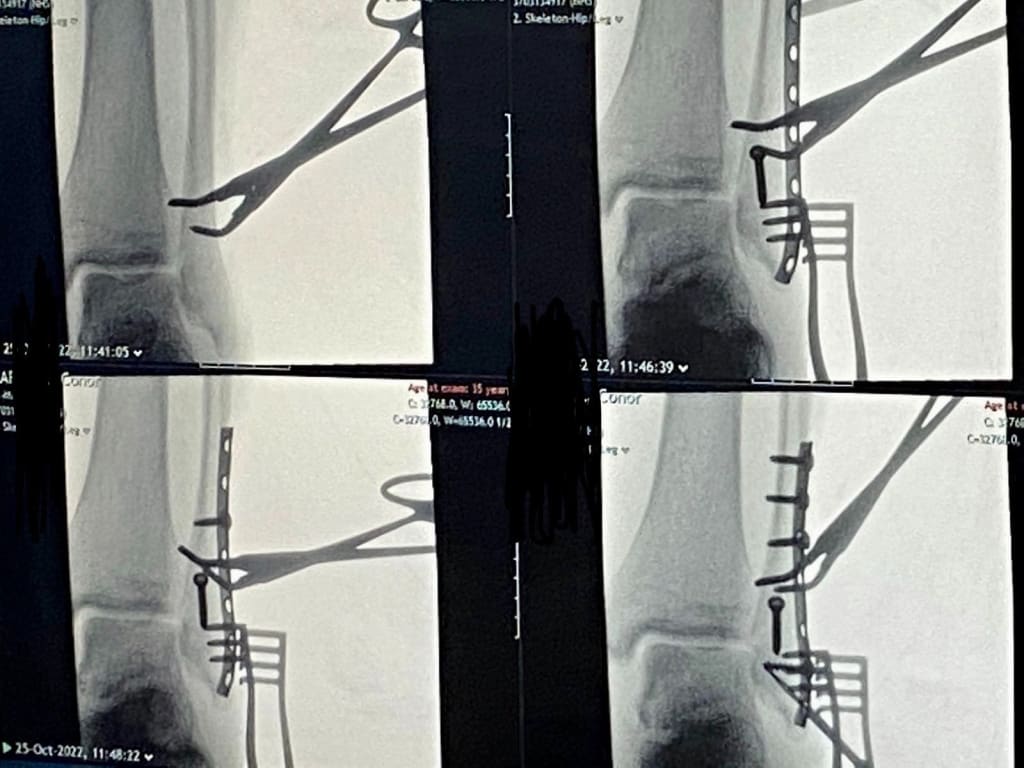

My Left Hoof.

I’m considering going to court

To sue for a most grievous tort.

When they pieced back my hoof

They were somewhat aloof

For I find I’m a half-inch more short!